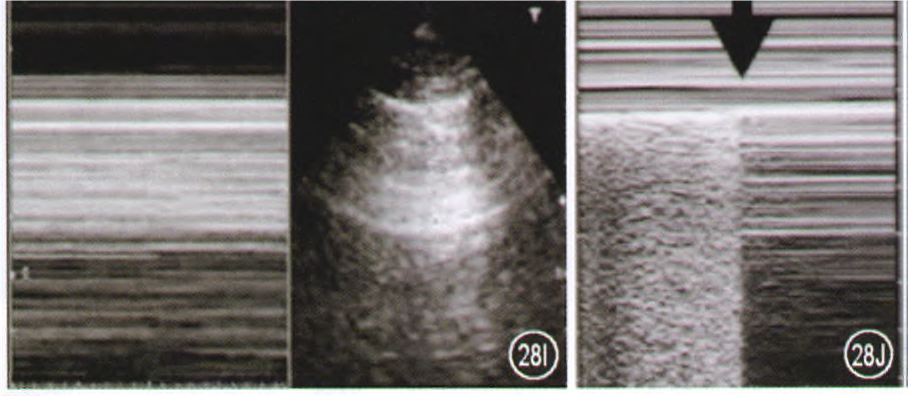

异常肺的超声表现

(1)条码征+肺点—气胸:异常肺的超声表现主要取决于气/水比例的变化引起的不同病理变化。以气胸为例,肺滑动征消失时,脏层胸膜和壁层胸膜无相对运动;M模式下表现为平行的水平线。所以与之前的沙滩征不同,这种横纹/条纹会一直出现,即为“条码征”(下图右)肺点是正常肺和气胸的交界点,它是诊断气胸的金标准。吸气时可见正常肺表现,呼气时胸膜滑动消失,M超呈条码征。所以气胸的超声表现即为条码征+肺点

图片

(2)B线—肺水肿:如果水增多就会产生B线。以肺水肿为例,B线是界限清楚的纵行伪影,起源于胸膜,延伸至屏幕远端,无衰减,其随胸膜滑动而滑动;其可消除A线,提示肺水含量增加;后侧胸部的B线可能是生理性的(见于28%的健康人),如果双上肺都有弥漫的B线,则提示肺水肿。